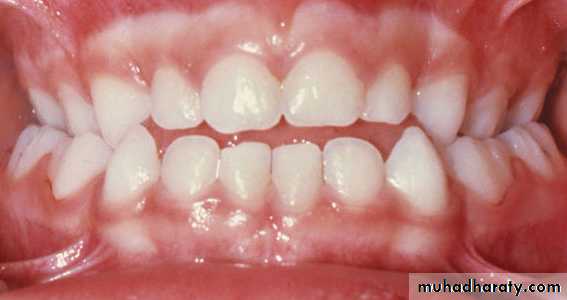

Bilateral crossbite